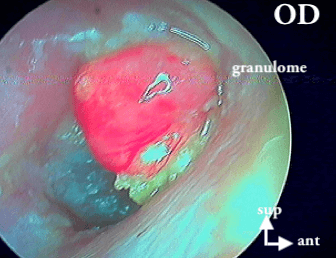

6 GRANULOME

Post-otitique si dans le conduit auditif externe distal alors otite externe, sinon otite moyenne aiguë, ATTENTION si proche du tympan cela peut cacher un cholestéatome ou une otite moyenne chronique non cholestéatomateuse.

Mais aussi du granulome péri-tympannique qui cache aussi un cholestéatome (revoir les patients!):